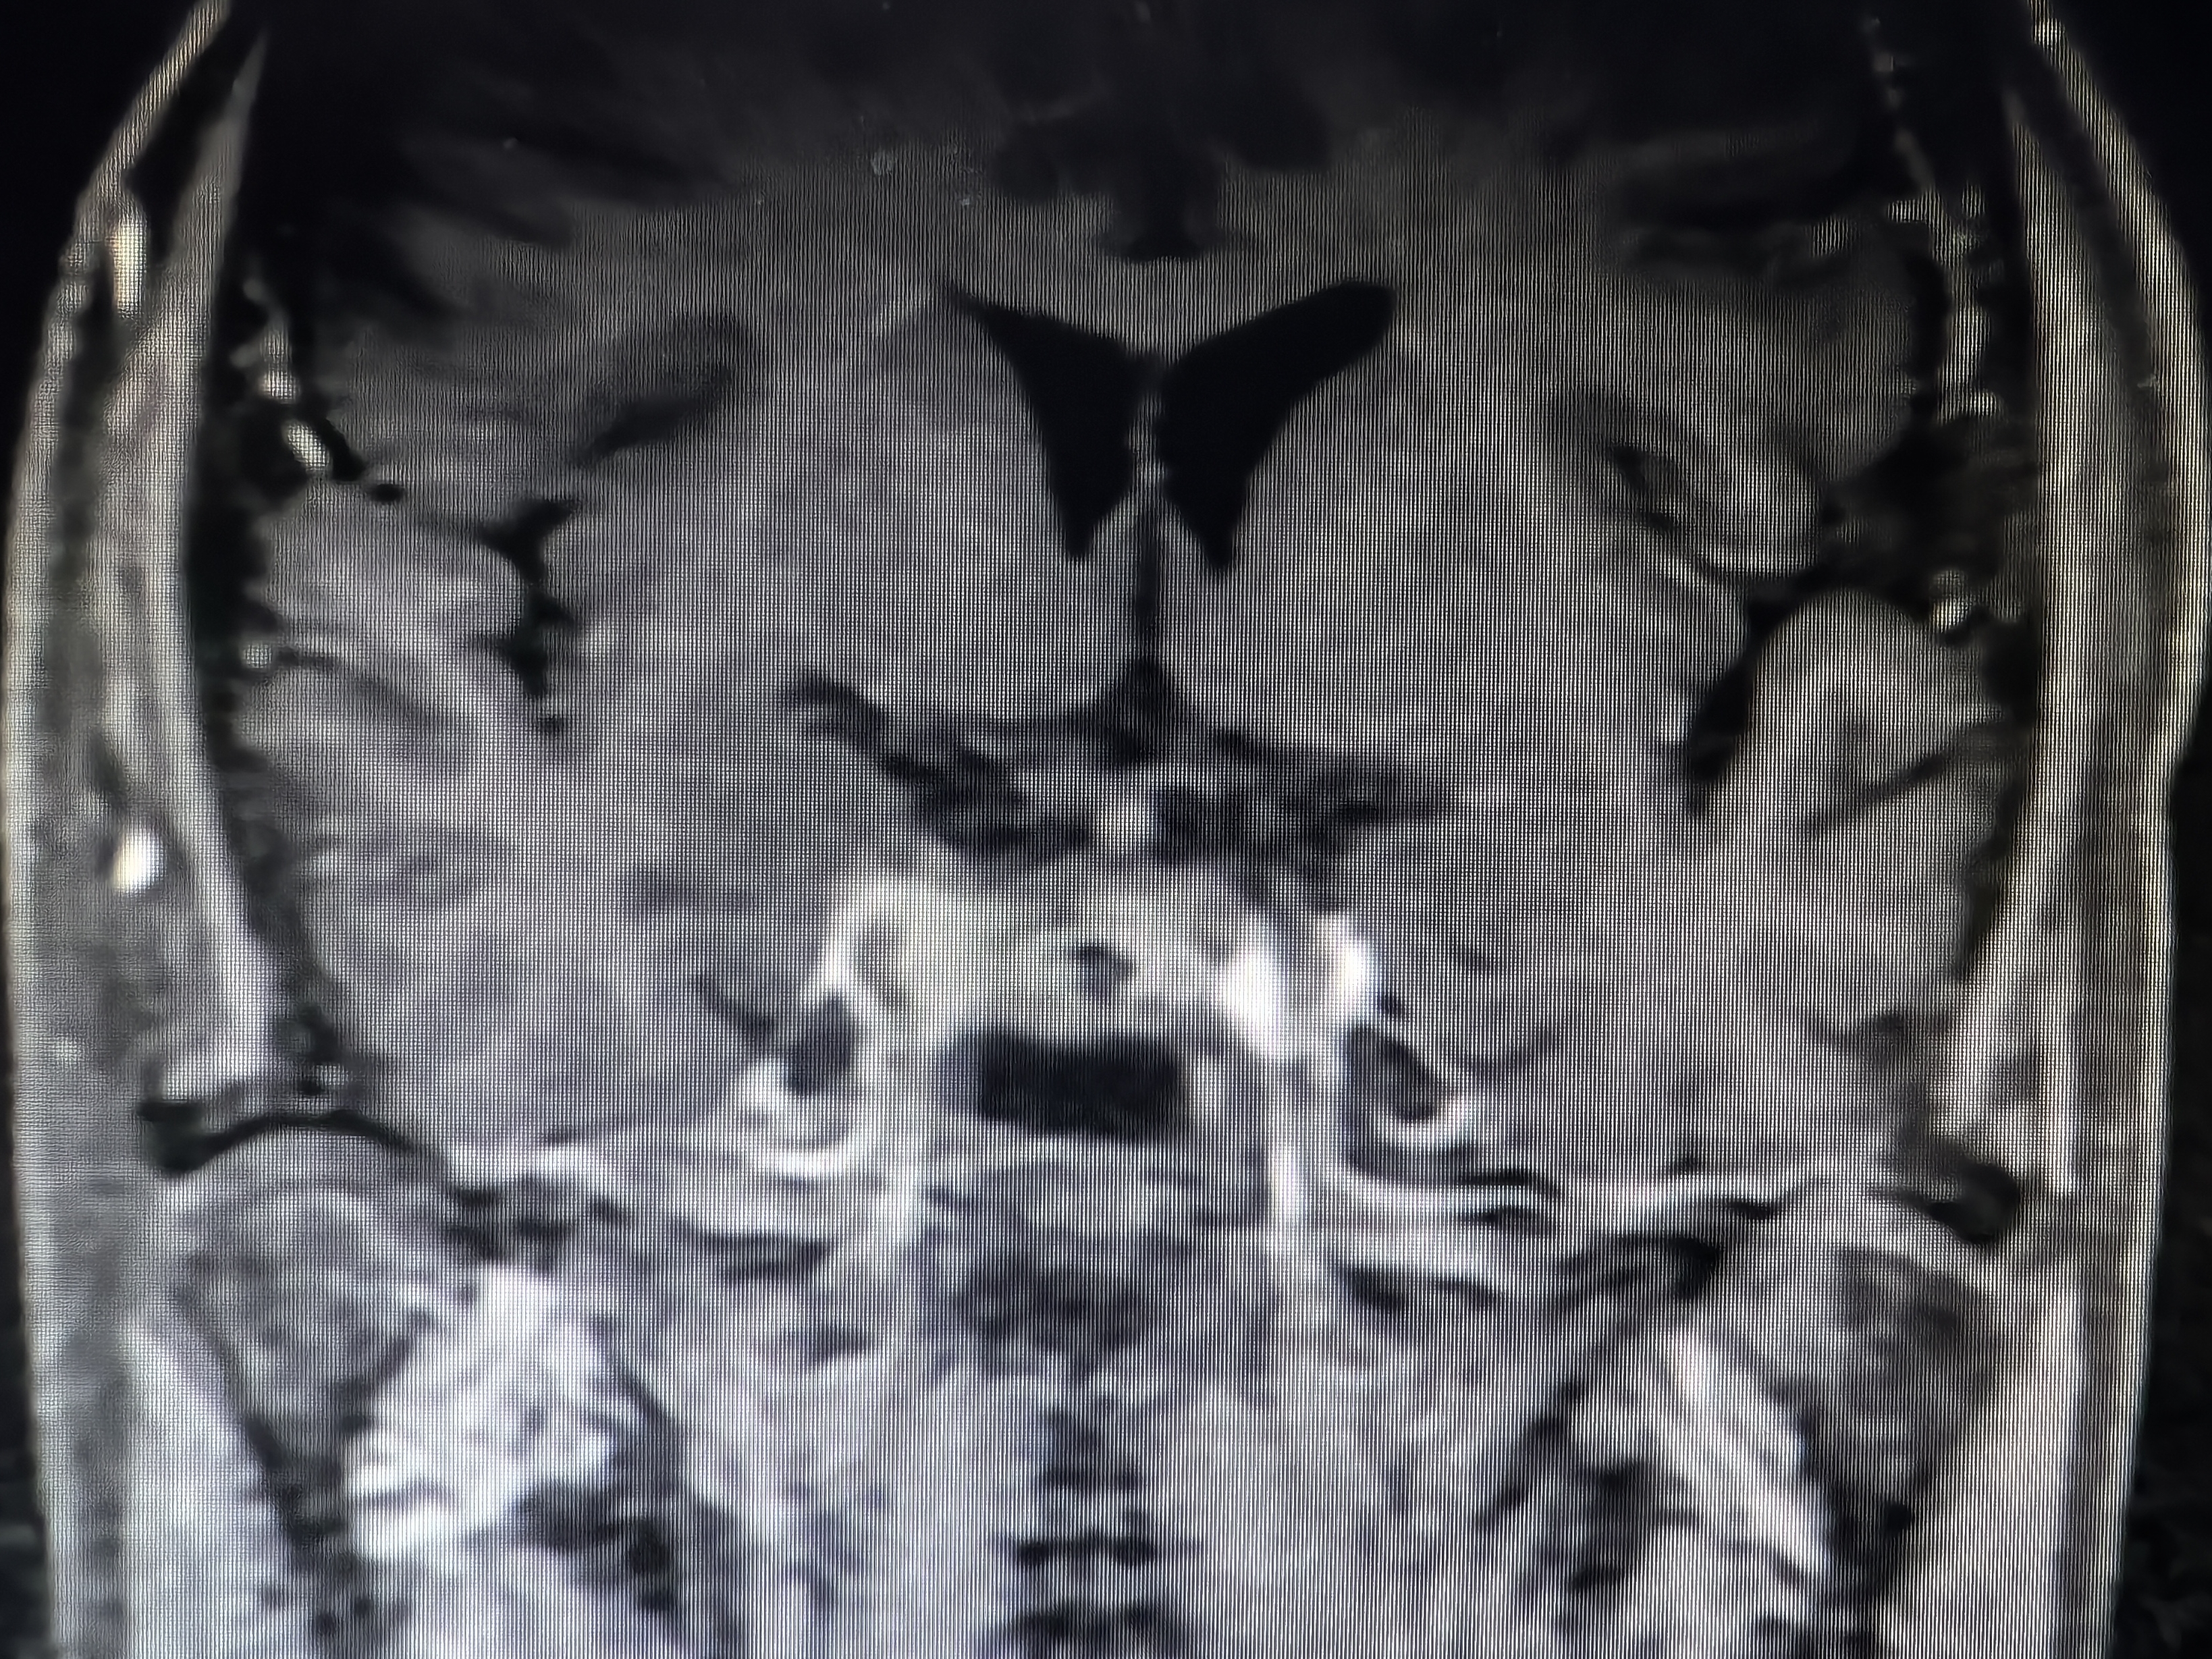

下面展示本病房几例病例:

肿瘤不大,重在规范。

病例一